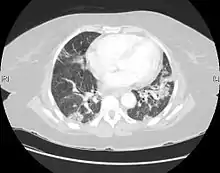

CT scan of a patient with UIP. There is interstitial thickening, architectural distortion, honeycombing and bronchiectasis. | |

UIP may be diagnosed by a radiologist using computed tomography (CT) scan of the chest, or by a pathologist using tissue obtained by a lung biopsy.

Radiologically, the main feature required for a confident diagnosis of UIP is honeycomb change in the periphery and the lower portions (bases) of the lungs.[3]

On high-resolution computed tomography (HRCT), the following categories, depending on imaging findings, have been recommended by a collaborative effort by the American Thoracic Society, European Respiratory Society, Japanese Respiratory Society, and the Latin American Thoracic Society:[4]